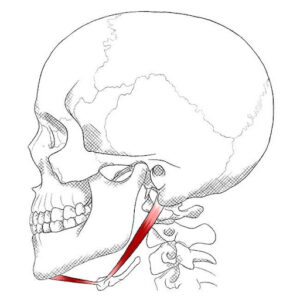

El músculo digástrico es un pequeño pero poderoso músculo ubicado debajo de la mandíbula. Se compone de dos vientres musculares (anterior y posterior) y es esencial para funciones tan cotidianas como hablar, masticar y tragar.

Cuando este músculo está tenso o sobrecargado, pueden aparecer síntomas que afectan a la calidad de vida de muchas personas:

✔ Dolor mandibular y sensación de tensión al abrir la boca.

✔ Cefaleas y molestias en la sien debido a su conexión con otros músculos de la cabeza.

✔ Dificultad para tragar (disfagia) o sensación de que los alimentos se atascan.

✔ Ronquera o pérdida de voz por la tensión indirecta en los músculos de la garganta.